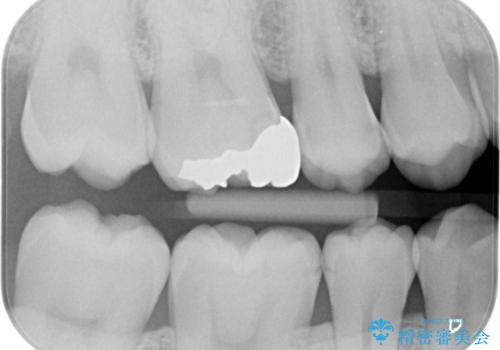

- 銀歯を白くしたいとの事で来院。

銀歯を除去し拡大鏡下でカリエスがない事を確認した後、e-maxインレーにて治療を行いました。